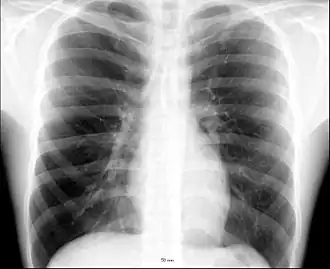

.jpg)

Different types of diseases or conditions that affect the chest include pleurisy, flail chest, atelectasis, and the most common condition, chest pain. These conditions can be hereditary or caused by birth defects or trauma. Any condition that lowers the ability to either breathe deeply or to cough is considered a chest disease or condition.

The major pathophysiologies encountered in blunt chest trauma involve derangements in the flow of air, blood, or both in combination. Sepsis due to leakage of alimentary tract contents, as in esophageal perforations, also must be considered. Blunt trauma commonly results in chest wall injuries (e.g., rib fractures). The pain associated with these injuries can make breathing difficult, and this may compromise ventilation. Direct lung injuries, such as pulmonary contusions (see the image below), are frequently associated with major chest trauma and may impair ventilation by a similar mechanism.